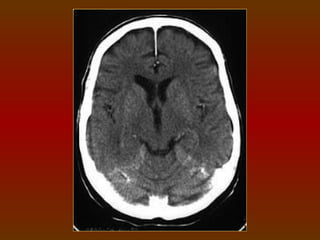

CORTE 6

a) Lobo frontal

b) Corno frontal do ventrículo lateral

c) Lobo parietal

d) Plexo coróide (calcificado)

e) Lobo occipital

f) Cápsula interna

g) Núcleo caudado